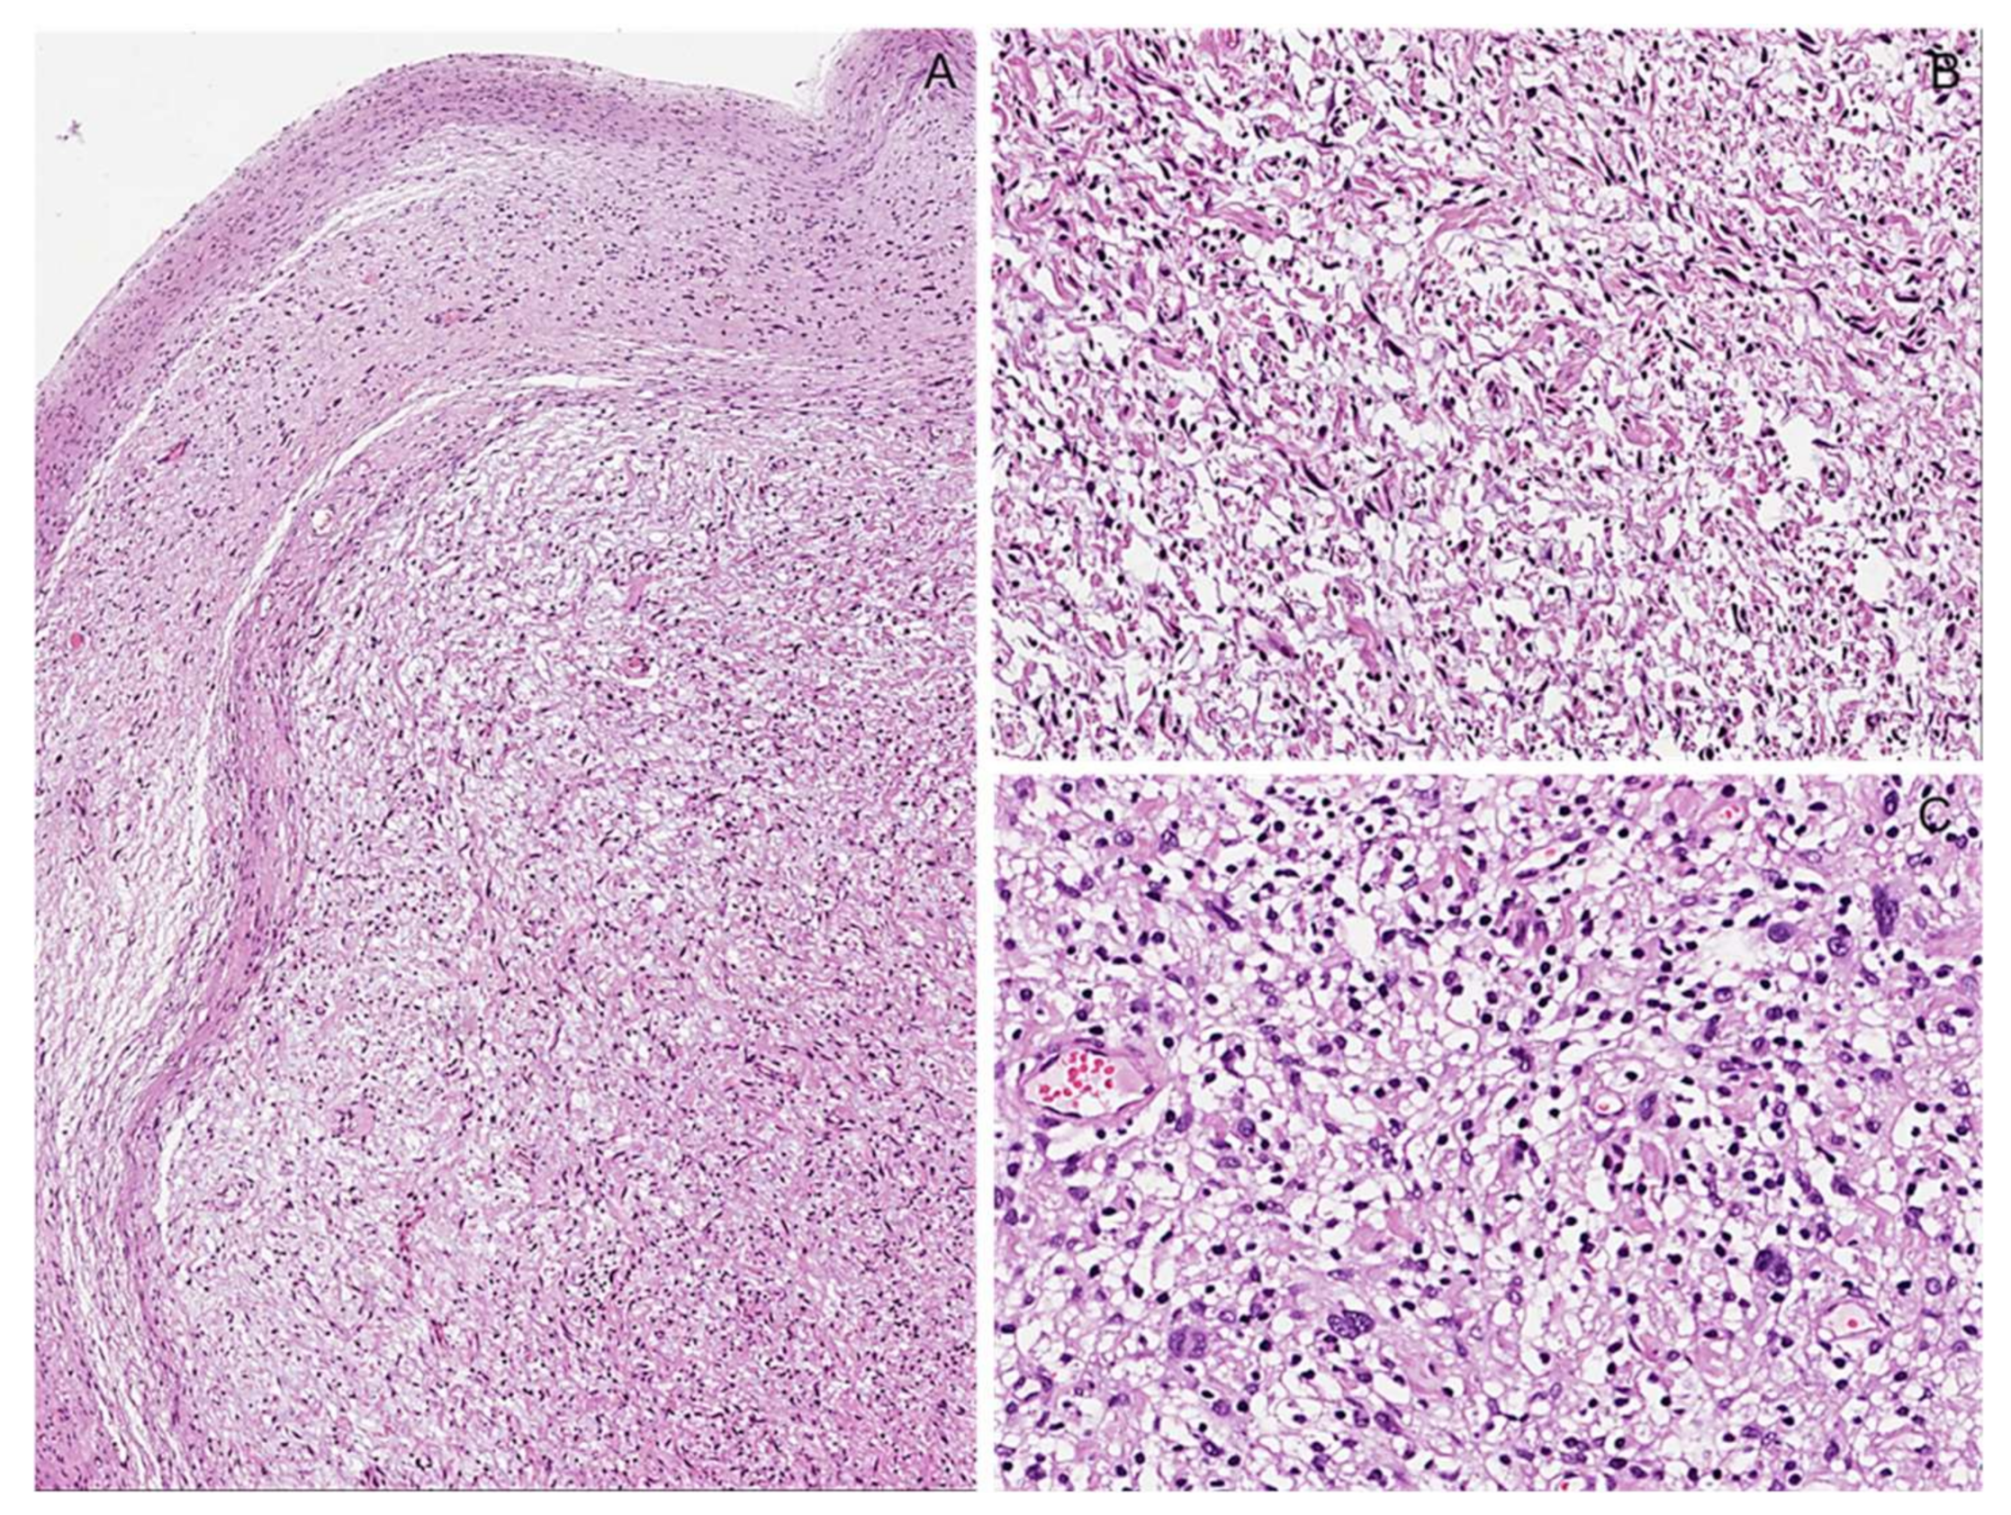

6.3. Cellular Schwannoma

Immunohistochemical Features